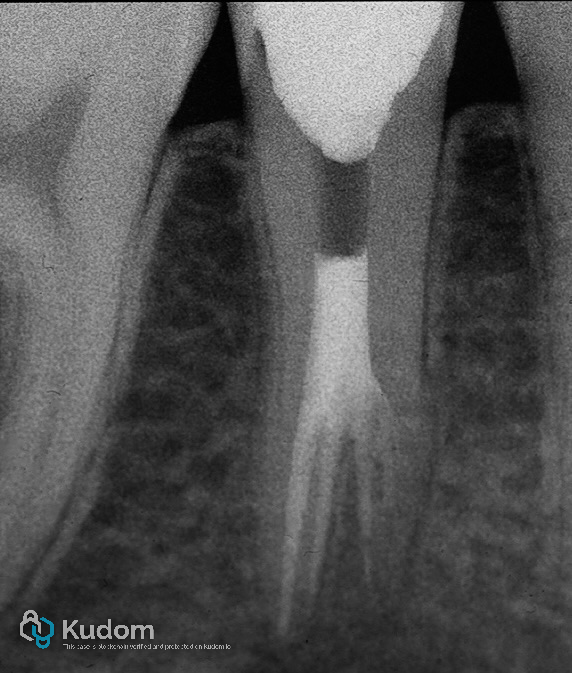

Patient Presentation:

A 19-year-old male patient presented with a severely compromised tooth 45, characterized by an extensive carious lesion leading to the complete loss of the clinical crown. Despite the advanced structural damage, the tooth was asymptomatic upon clinical and radiographic examination.

Fig. 2

Diagnosis and Treatment Plan:

Given the extent of coronal destruction, non-surgical root canal therapy was indicated, followed by a post-endodontic core build-up and definitive restoration. The objective was to preserve the remaining tooth structure and restore full function and aesthetics.